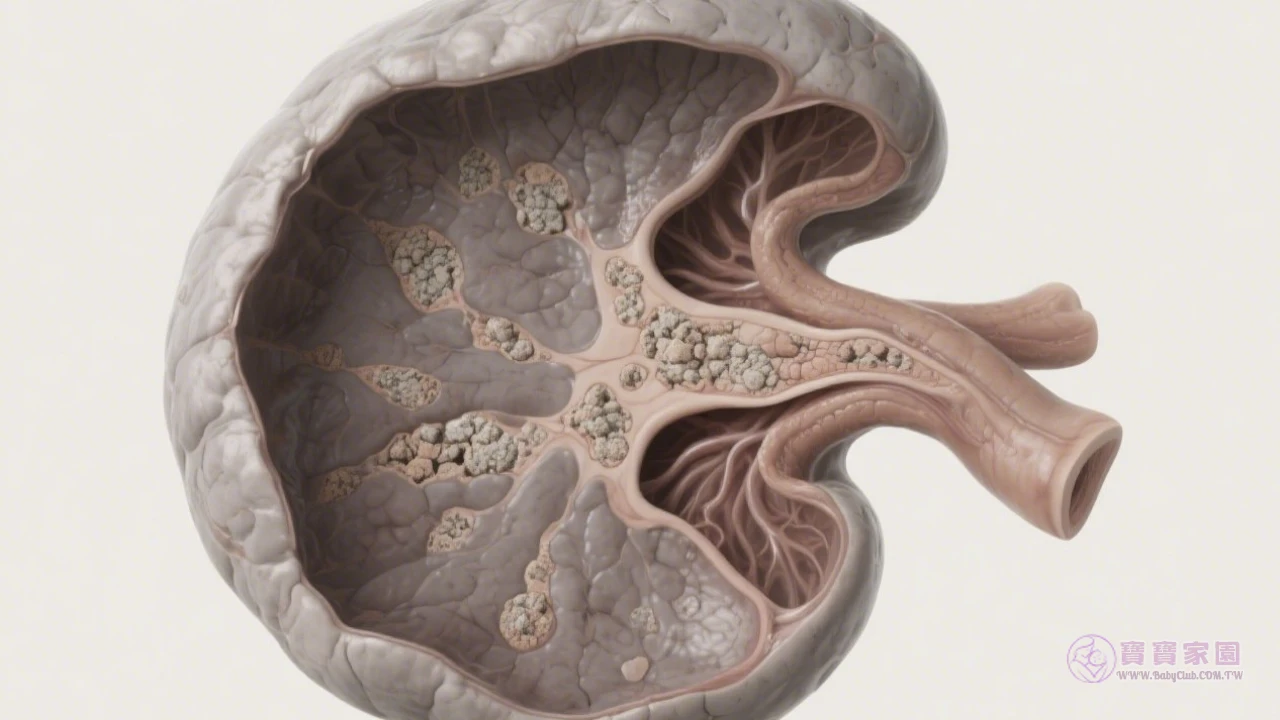

懷孕第10週指南|掌握寶寶發育關鍵期與產檢重點2走到懷孕第10週的裡程碑,距離與寶寶見面還有30週!近期你可能發現孕期症狀有了新變化,來看看醫師推薦的緩解技巧,瞭解本週最重要的NIPT產檢項目與育嬰假資訊。 寶貝正在快速成長期 本周寶寶的大小約像顆草莓,身長接近3公分。雖然孕程因人而異,多數媽媽在此階段會經歷: 本週產檢核心項目:NIPT檢測 婦產科醫師李欣怡指出:「以往非侵入性胎兒染色體檢測(NIPT)...標籤:懷孕第3個月